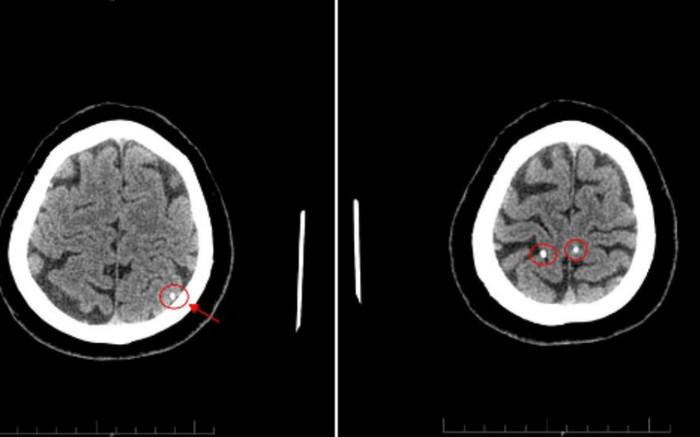

Có biểu hiện đau nhức đầu nhiều ngày, ông T. đến khám tại Trung tâm y Tế huyện Tân Sơn được các Bác sĩ thăm khám và chỉ định chụp Cắt lớp vi tính sọ não phát hiện ấu trùng sán làm tổ trong não.

Trung tâm Y tế Tân Sơn (Phú Thọ) cho biết, bệnh nhân T. (56 tuổi) vào thăm khám ngày 23/6. Ông có biểu hiện đau nhức đầu được các bác sĩ thăm khám và chỉ định chụp Cắt lớp vi tính sọ não.

Hình ảnh chụp cắt lớp cho thấy nang ký sinh trùng trong não bệnh nhân. Ảnh: BVCC

Sau khi thăm khám, bác sĩ chuyên khoa Chẩn đoán hình ảnh kết luận trong sọ não bệnh nhân T có "Hình ảnh nang ký sinh trùng (ấu trùng sán não - neurocysticercosis)". Theo bệnh viện, trước đó Bệnh nhân T. có thói quen ăn đồ sống là gỏi cá.